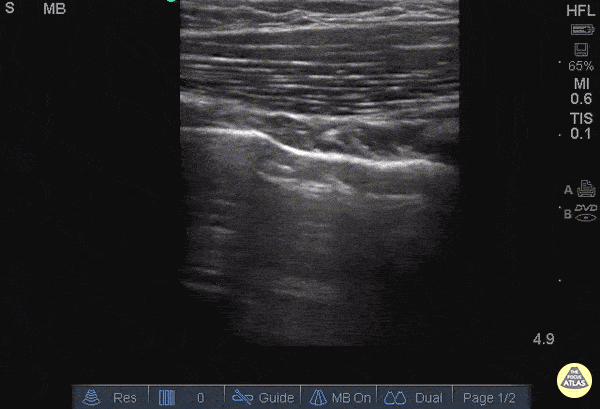

25 y/o female in and MVA with hypotension, hypoxia. Normal lung with A lines can briefly be seen until the sonographer moves the probe superiorly to reveal and area of B lines adjacent to A line. In the setting of trauma this is consistent with Pulmonary Contusion. Images: Dr. Catharine Bon - Kings County Hospital Emergency Medicine